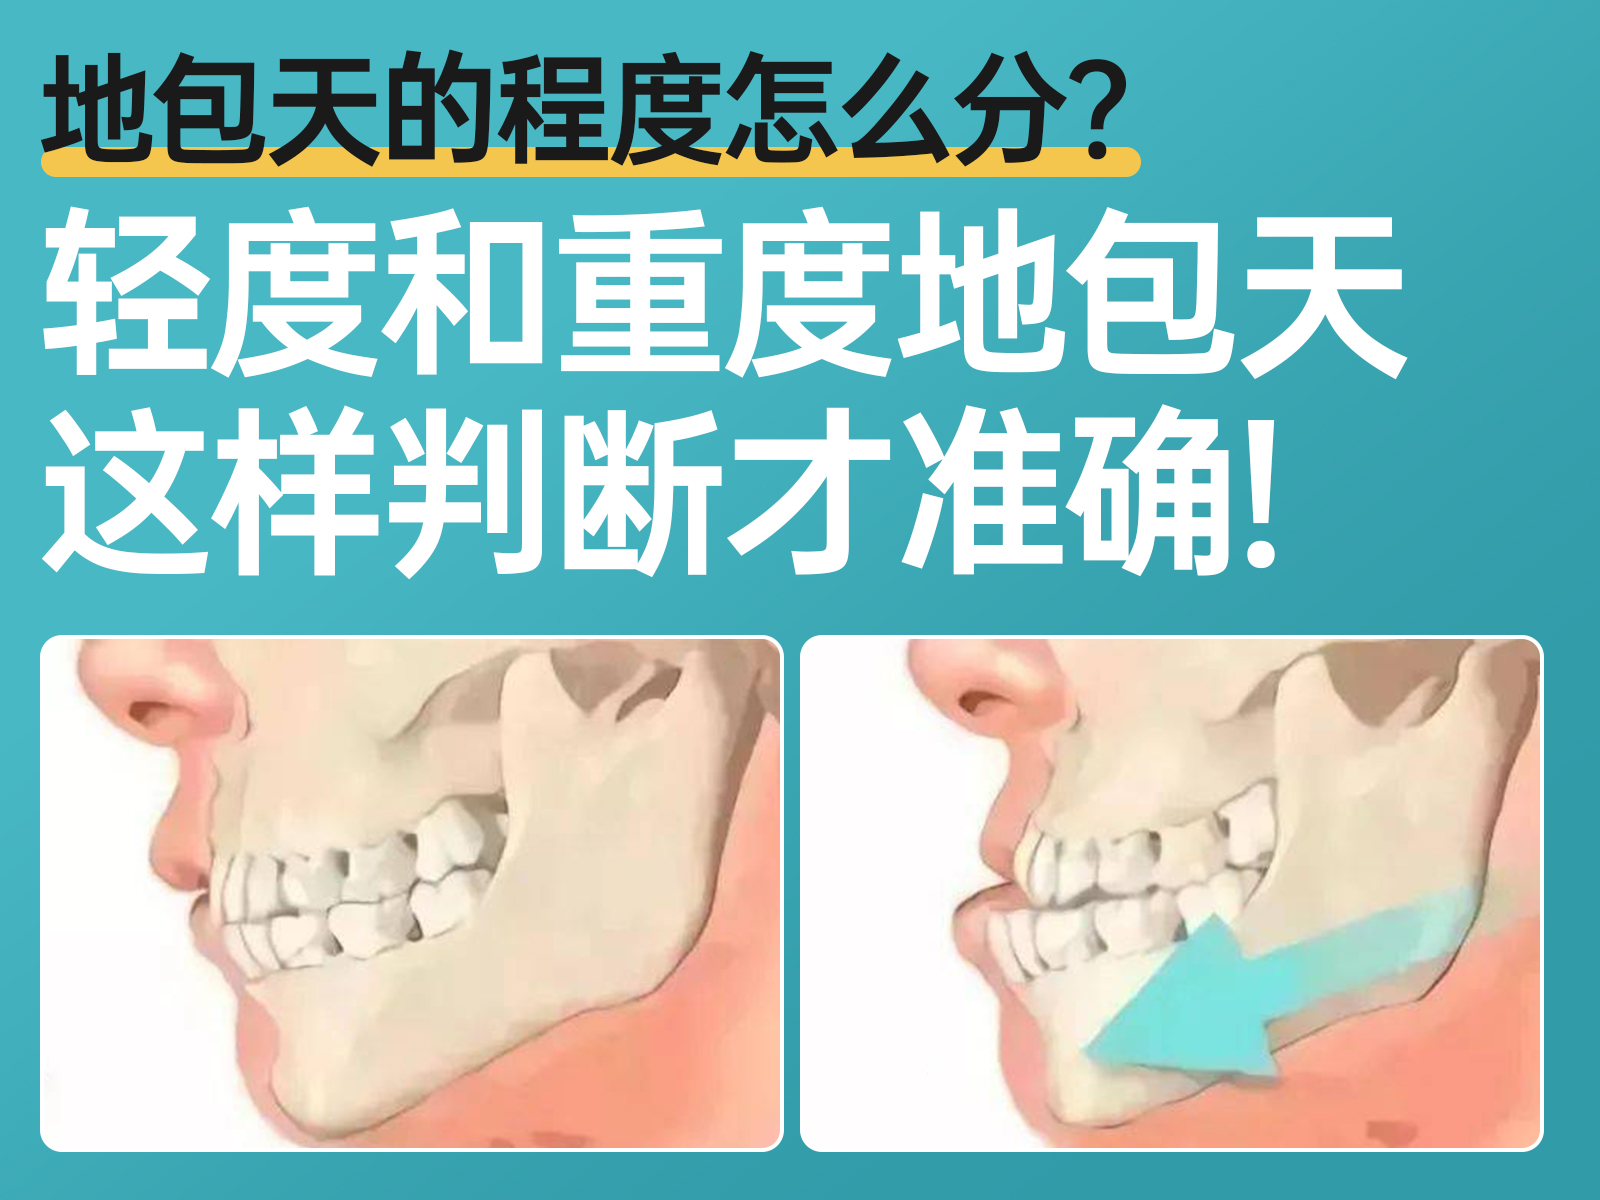

地包天的程度怎么分?轻度和重度地包天这样判断才准确!

你可能不知道,实际上地包天(下颌前突)也有不同的严重程度分类。那么,地包天通常分为哪几种类型呢?今天,开立特小编将为你详细介绍地包天的不同程度分类,帮你轻松判断自己属于轻度、中度还是重度地包天。一、地包天的分类方法:地包天根据其严重程度通常分为三种主要类型:牙源性地包天:这种类型主要由于前牙区牙齿的排列异常引起,属于牙齿本身的问题,导致前牙出现反颌现象。功能性地包天:这类地包天通常出现在儿童身上,